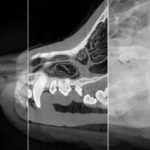

Dental Care

Radiography